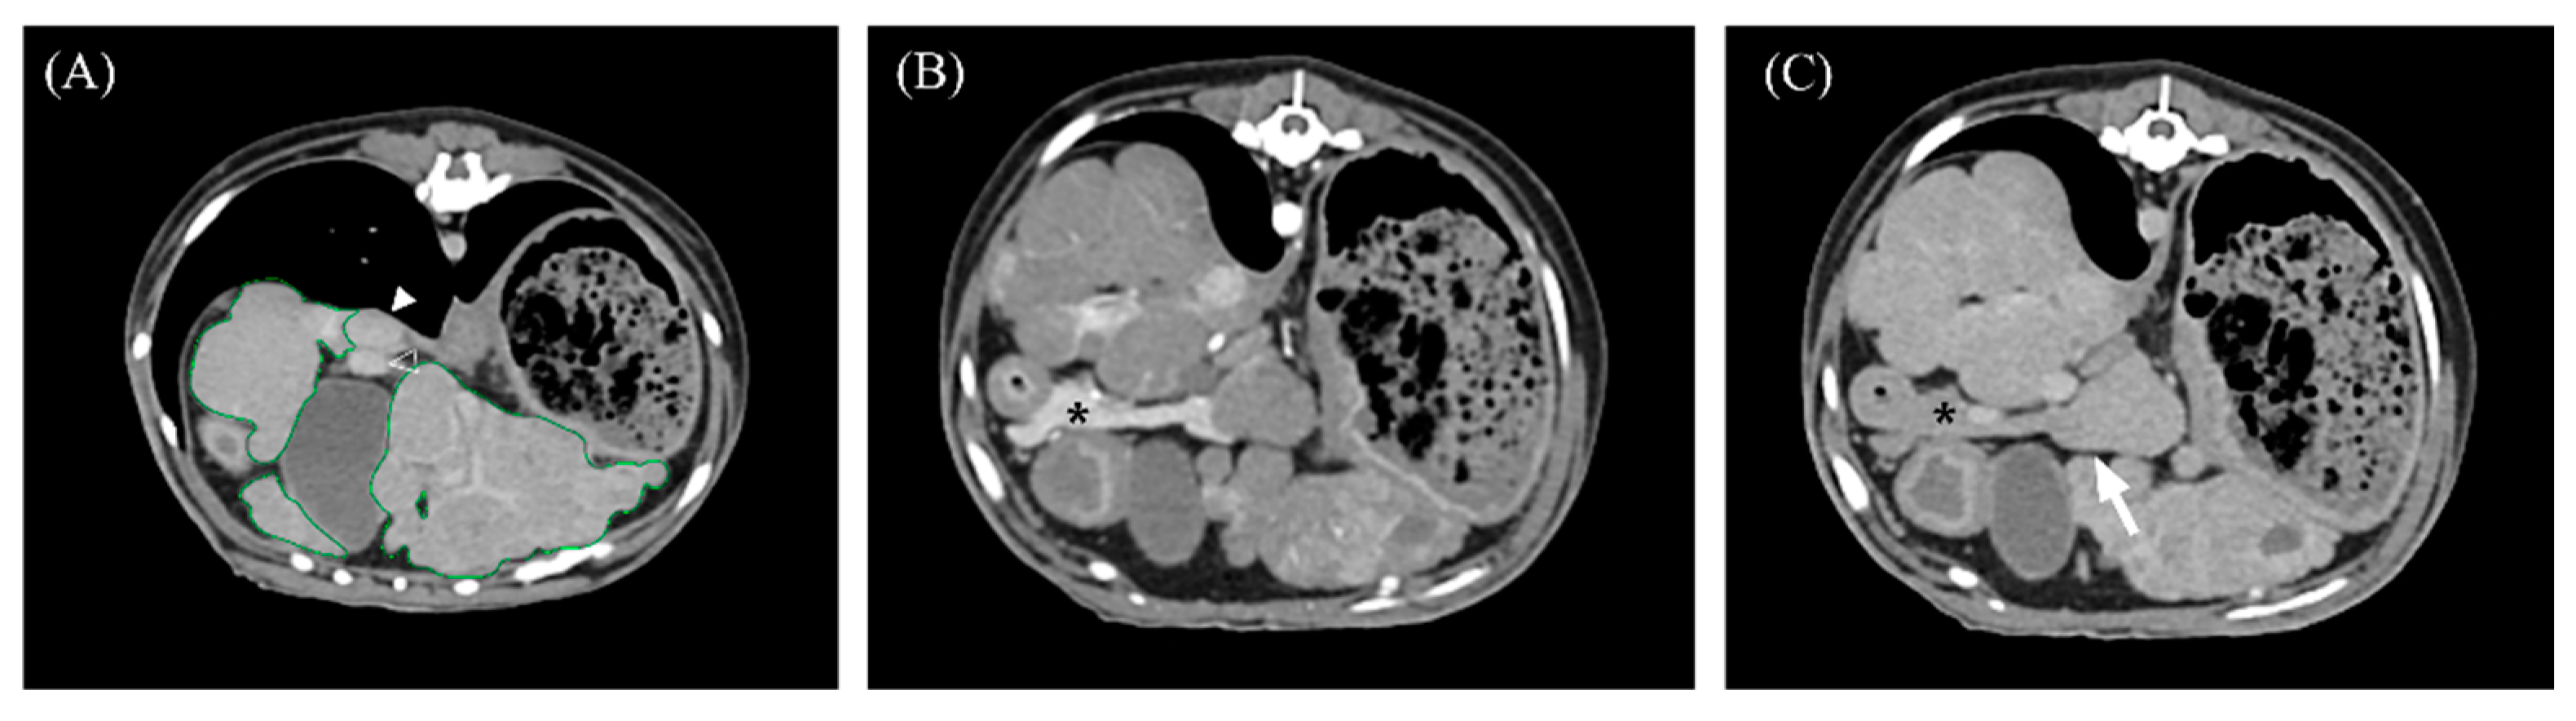

3.2. Qualitative Computed Tomographic Features

| Periportal lymph node enlargement (>5 mm) | Present | 11/16 (68.8%) | 8/11(72.7%) | 3/5 (60%) | 1.000 |

| Absent | 5/16 (31.3%) | 3/11 (27.3%) | 2/5 (40%) | ||